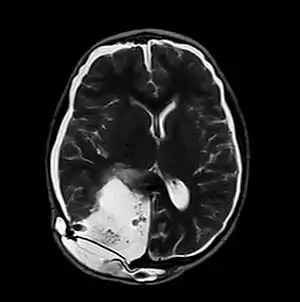

| MRI of Pseudomeningocele in 8 years old male patient | |